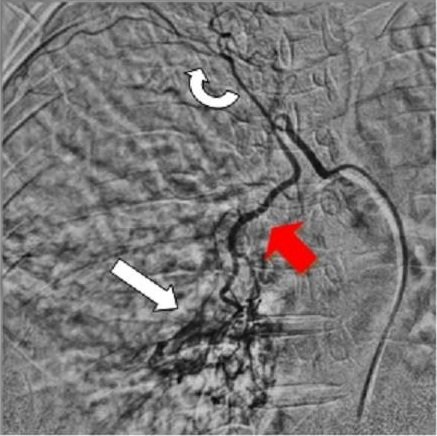

Vascular (Artery & Vein) Interventions

Brain Interventions